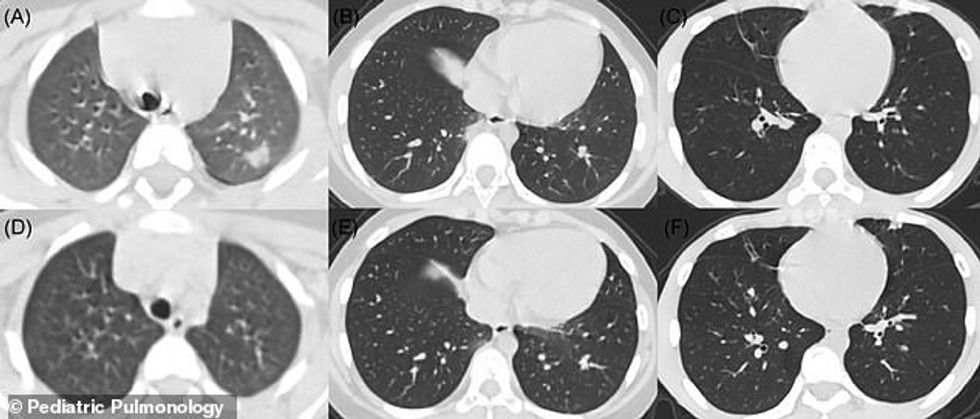

Mjekët, të udhëhequr nga radiologu Alexandra Fuust, vendosën të krahasojnë dëmin e COVID-19 me sëmundje të tjera të ngjashme me frymëmarrjen.

Ata shikuan SARS dhe MERS, të dy coronaviruset e lidhura, H1N1, dhe EVALI – një gjendje e zbuluar rishtazi e lidhur me thithjen e tymit.

Mjekët që qëndronin pas këtij studimi, të botuar në “Pulmonologjinë Pediatrike”, thanë se ‘konsolidimi me shenjat rrethore ishte i zakonshëm në pacientët pediatrikë të cilët ishin të ndryshëm nga të rriturit’. /Dailymail